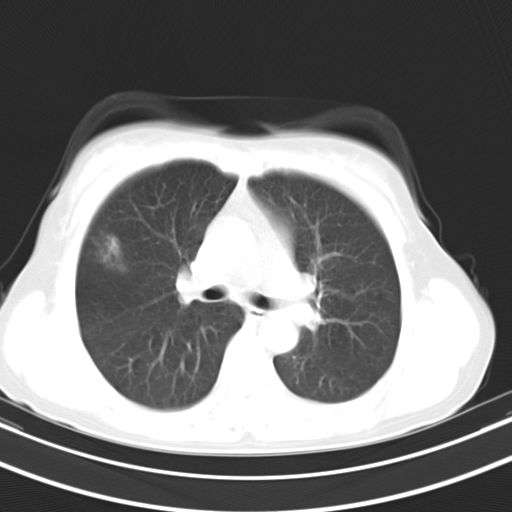

女,47岁,咳嗽胸痛一个星期,我们考虑肺结核,左下肺病灶肿瘤像不像,请高手指点。急。

右肺考虑炎症,建议抗炎后复查,左肺下叶考虑肺不张。

炎性灶;【1楔状实变影,有支气管气象,2近端纹理影增重】

右肺上叶前段积左肺舌叶炎症,建议严格抗炎后2周复查!

右肺上叶尖后段班片影不能出外肺结核。左肺舌叶三角形实变影,增强明显。考虑炎性病变

右肺为炎性改变,左肺病灶影像所见1、楔状实变影,边缘呈刀切样,见支气管气象,2、近端纹理影增重。

两肺病变考虑炎症可能性大。(左肺病变呈楔状实变影,有支气管气象,近端纹理影增重)。